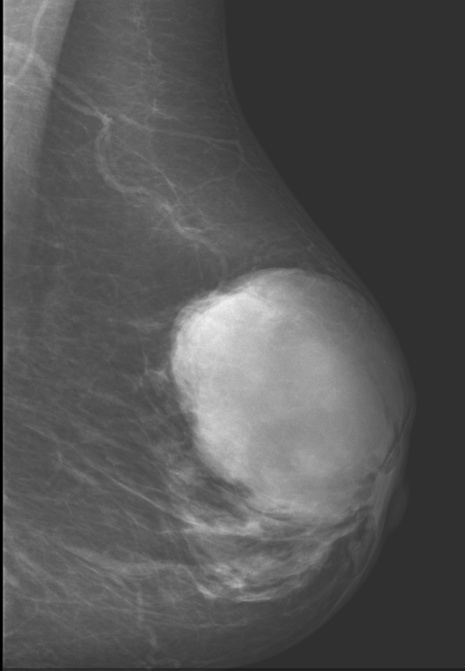

Fibroadenoma

_is a benign tumor of fibrous tissue and glands that is the most common benign neoplasm of the breast. It most commonly occurs in women in their 20s and 30s.,

_The gross appearance of fibroadenomas presents as a well-circumscribed, grayish-white, rubbery nodule with cleft-like spaces inside.,

Fibroadenoma: noncalcified rounded mass in UOQ left breast

Wider than tall

breast cancer grow vertical

_Is characterized by large, high-grade cells growing in sheets with associated lymphocytes and plasma cells. These tend to grow as a well-circumscribed mass that can resemble a fibroadenoma on mammography. Have a relatively good prognosis.,